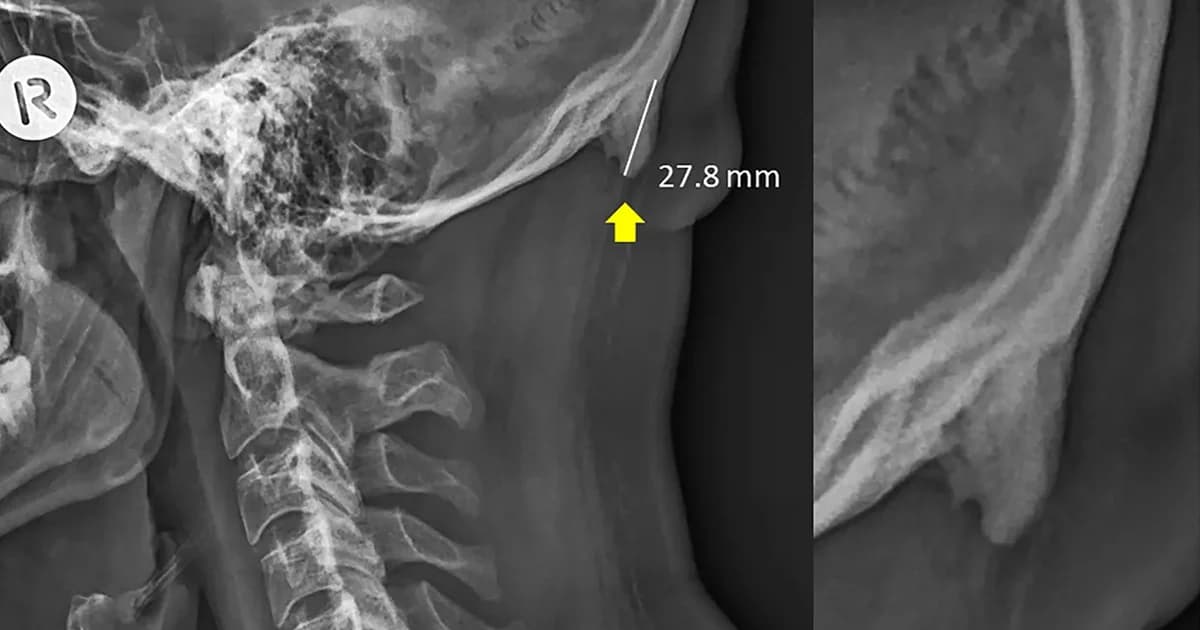

David Shahar และ Mark Sayers สองนักวิจัยจาก University of the Sunshine Coast ในประเทศออสเตรเลีย ได้ตีพิมพ์งานวิจัยชิ้นหนึ่ง ซึ่งนำฟิล์ม X-ray ของวัยรุ่นอายุ 18-30 ปี จำนวน 218 ภาพมาวิเคราะห์ และพบว่าในวัยรุ่นกลุ่มนี้ มีถึง 41% ที่มีกระดูกที่มีลักษณะเหมือนเขา (horn-like) งอกออกมาจากบริเวณใต้กะโหลกศีรษะเหนือท้ายทอย โดยกระดูกส่วนที่งอกเกินมานี้มีความยาวตั้งแต่ 10 มิลลิเมตร ถึง 30 มิลลิเมตร

ในการทำวิจัยดังกล่าว สองนักวิจัยชาวออสเตรเลียได้ผนวกรวมเอาการแสกน MRI เข้าไปเป็นส่วนหนึ่งในการวิจัยด้วย และได้ข้อสรุปว่า กระดูกที่งอกออกมาจากกะโหลกดังกล่าวนั้น ไม่ได้เป็นผลมาจากกรรมพันธุ์หรืออาการบาดเจ็บ